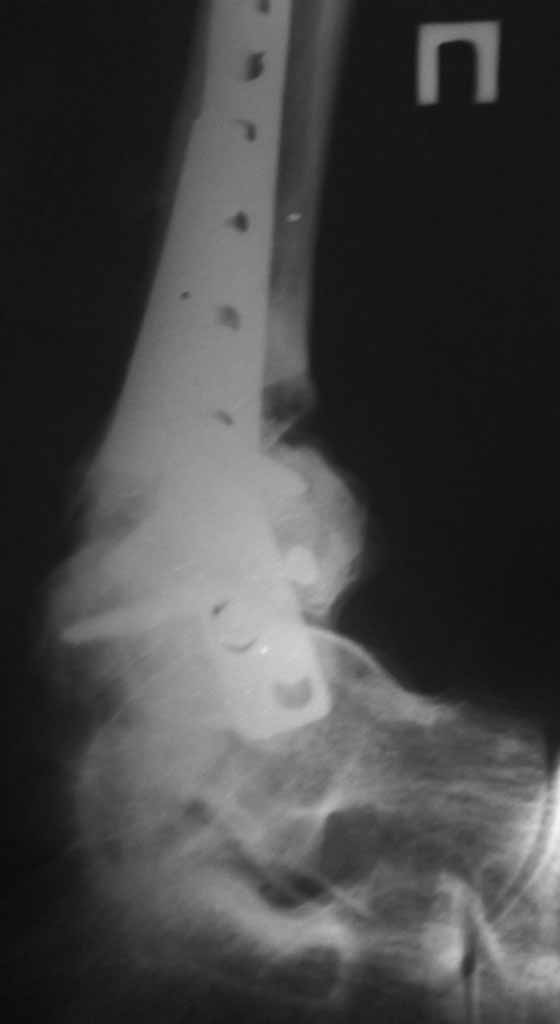

Помогите с дальнейшей тактикой лечения. Больной 57 лет. Травма в мае 2009(упал фундаментный блок на обе н.конечности. Операция в мае пластинкой.

Нагрузку начал давать через 4 месяца. Через 1,5 месяцев появился отек конечности. На контрольном Р-снимке сломанная пластинка. Больной ходит, прихрамывая на эту конечность. Беспокоит отек,боль.Снимки прилагаются. Зараннее спасибо.Николай.

Удаление металлоконструкции,остеотомия м/берц. к-ти(снимок в прямой пр.?)АВФ по Илизарову с фиксацией г/ст.сустава,дозированная нагрузка в АВФ.Удачи!